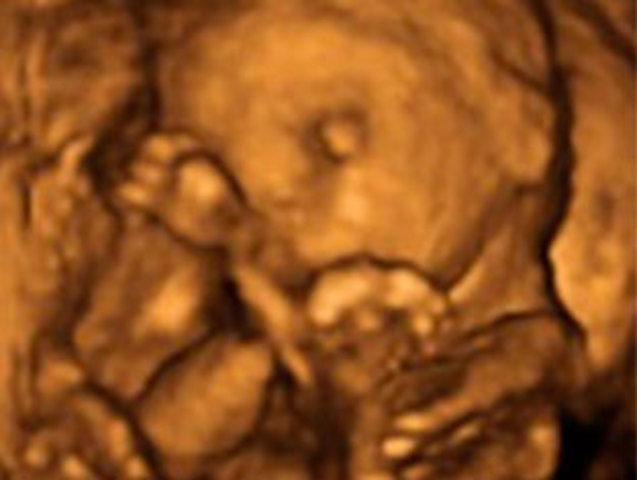

El bebé pesa ya 700 gramos y mide 22 centímetros desde la cabeza al final de la columna.

Los párpados del niño se abren y se pueden ver los ojos. La lengua sale de la boca y se mueve hacia los lados, sonríe y empieza a hacer gestos.

• Vigésima sexta semana.

Vigésima sexta semana.

El bebé pesa unos 900 gramos y mide alrededor de 23 centímetros desde la cabeza hasta el final de la columna, sin contar las piernas.